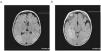

Se realizó hemograma, coagulación, perfil hepatorrenal y gasometría, con resultados normales. La tomografía computarizada craneal fue normal. El líquido cefalorraquídeo (LCR) mostraba un recuento de leucocitos de 41céls./mm3 (el 60% polimorfonucleares), glucosa de 66mg/dl y proteínas de 0,63g/l; se recogieron muestras para cultivo de bacterias y PCR (polymerase chain reaction 'reacción en cadena de la polimerasa') para virus. El paciente ingresó en la unidad de cuidados intensivos donde se inició tratamiento con cefotaxima, aciclovir y ácido valproico. La PCR para el virus del herpes simple (VHS) tipo 1 en LCR fue positiva y se mantuvo el tratamiento con aciclovir 20mg/kg i.v. cada 8h durante 21 días. El electroencefalograma (EEG) mostró PLED (periodic lateralized epileptiform discharges ‘descargas epileptiformes lateralizadas periódicas’) en la región temporoparietal derecha. En la resonancia magnética (RM) (figura 1) se observó afectación parenquimatosa corticosubcortical muy extensa en el hemisferio derecho y el tálamo. Al alta, el paciente presentaba un nivel de consciencia y seguimiento visual normales y se mantenía sentado, aunque persistía una interacción escasa e inatención y hemiparesia izquierdas. Al tercer día, tras finalizar el tratamiento, en el paciente se desarrolló un violento síndrome extrapiramidal con corea generalizada, balismo en los 4 miembros, protrusiones linguales y extrema irritabilidad, que sólo desaparecían con el sueño. Se añadió un deterioro neurológico global con pérdida del contacto visual y del control axial e hipotonía global. Se realizó otra RM sin que se observaran nuevas lesiones y punción lumbar con PCR negativa para el VHS. Se interpretó el cuadro como una recaída tardía de probable origen autoinmunitario, por lo que se lo trató con un ciclo de esteroides en altas dosis y un ciclo de inmunoglobulinas en dosis de 1mg/kg, sin mejoría evidente. Aunque no parecía una reactivación de la infección vírica, el paciente recibió aciclovir i.v. Se realizó vídeo-EEG, en el que no se observó actividad crítica asociada a los movimientos anormales. Los movimientos extrapiramidales eran tan continuos que obligaron a mantener al niño intubado y sedorrelajarlo inicialmente. Posteriormente, se lo trató con neurolépticos (haloperidol y tetrabenacina en altas dosis) sin clara respuesta. Se estudió la mutación (c.1660C>T) en el gen TLR3 (Toll like receptor 3 ‘receptor tipo Toll 3’), relacionada con la susceptibilidad de presentar encefalitis por VHS, pero el paciente no era portador.

Figura 1. a y b). Estudio de resonancia magnética. Planos axiales a través de (a) ambos hemisferios cerebrales y (b) del mesencéfalo y la fosa posterior en secuencia FLAIR (fluid attenuated inversion recovery). Obsérvese alteración de la señal, con prolongación de los tiempos de relajación (hiperintensidad) que afecta a los lóbulos temporales, especialmente al derecho (b), y a los occipitoparietales (a).